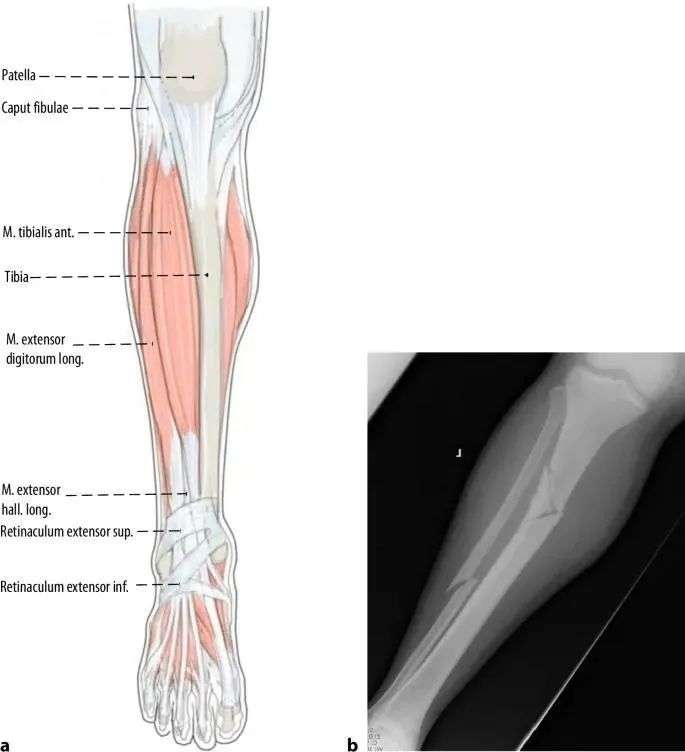

Основной причиной смещения при переломах проксимального отдела большеберцовой кости является деформация, вызванная растяжением сухожилия четырехглавой мышцы бедра во время сгибания колена и механическим конфликтом между кончиком ногтя и задней корой большеберцовой кости во время установки имплантата. Надколенник также препятствует осевому входу стержня в сагиттальной плоскости (рис. 1а, б). Поэтому другим распространенным методом введения в точку является медиальный парапателлярный разрез, в результате которого гвоздь вводится слегка медиально-латерально (рис. 1c и 2). Когда стержень входит в интрамедуллярный канал дистальнее перелома, проксимальная часть наклоняется в экзостоз (рис. 2). Наконец, напряжение покоя мышц передней камеры незначительно способствует эктропиону (рис. 3).

Рисунок 1 а, б. При использовании традиционного инфрапателлярного доступа надколенник предотвращает аксиальное вхождение стержня, что приводит к распространенной деформации переднего апикально-сагиттального выравнивания и эктропиона коронального выравнивания. c Интрамедуллярное выравнивание гвоздя выполнялось с использованием парапателлярного доступа.